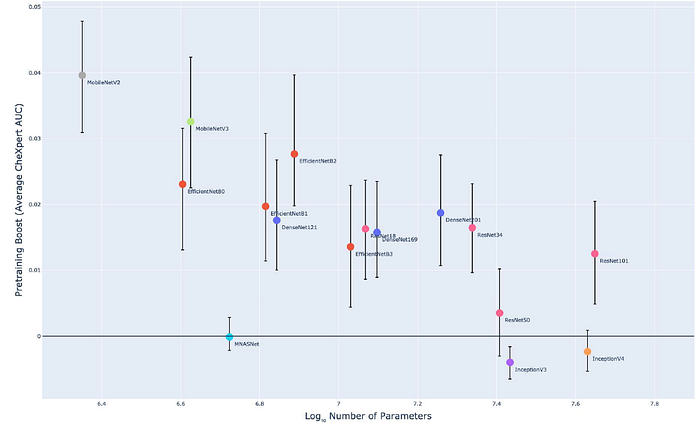

- The logarithm of the model size has a near linear relationship with CheXpert performance when no pretraining (Spearman 𝜌 = 0.79).

- However once with pretraining, the monotonic relationship is weaker (Spearman 𝜌 = 0.56).

Most models benefit significantly from ImageNet pretraining. Smaller models tend to benefit more than larger models (Spearman 𝜌 = −0.72).